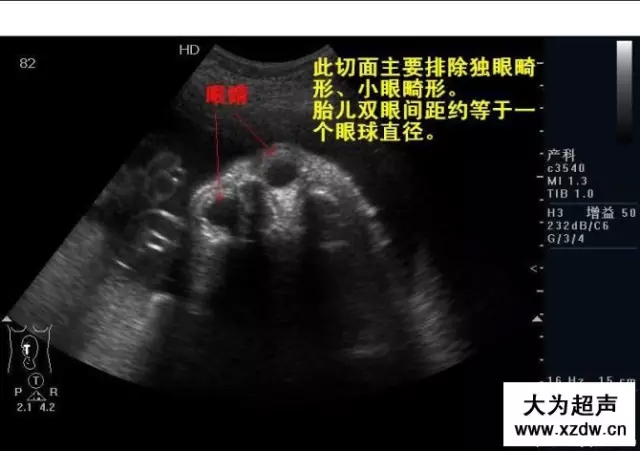

產(chǎn)科超聲正常圖片